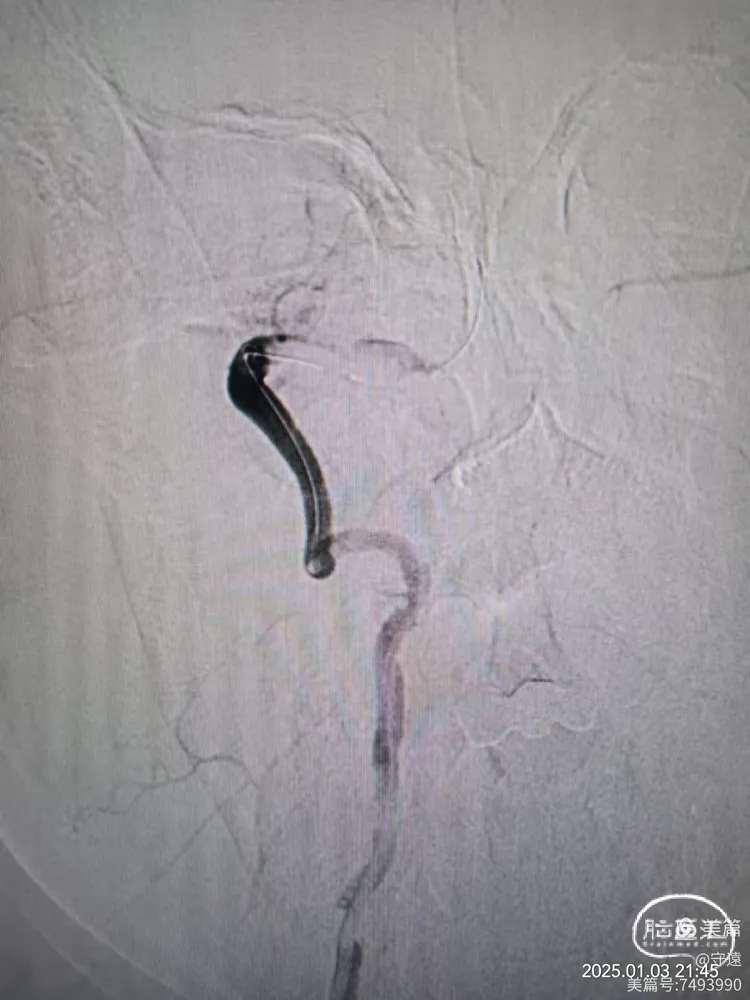

经桡动脉造影:左侧椎动脉起始终部中度狭窄。向颅内供血缓慢,v4段闭塞。

右侧椎动脉为优势椎,血流迟滞,V2以远未显影,考虑V4 闭塞。

微导管造影显示Ⅴ4狭窄。

微导丝携带2.5*15mm球囊在V4~基底动脉下段扩张。

撤出球囊血管,造影显示再次闭塞,考虑夹层或回弹可能。